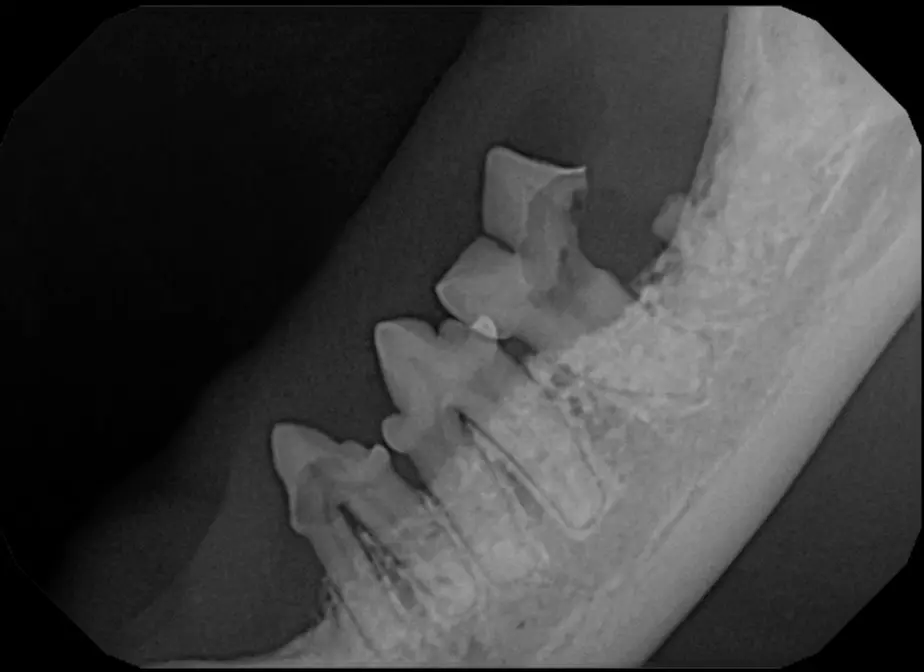

Surgical Extraction of Diseased Teeth

Periodontal disease is extremely common in dogs and cats. Over 80% of dogs and cats over two years of age have some degree of periodontal disease. Periodontal disease is best prevented by yearly professional dental cleanings starting at two years of age and at home brushing at least three times weekly. Brushing should begin at a very early age to allow your new pet to get used to regular brushing. In severe cases of infection or periodontal disease, the teeth may need to be surgically extracted. Extractions should always involve x-rays of the tooth first, as many teeth have multiple roots or may be diseased below where the eye can see. Extracting larger teeth in animals requires oral surgery, equivalent to removing wisdom teeth in people. It is vital that all of the tooth and roots be removed for the periodontal infection to resolve. In cases of important teeth with mild to moderate periodontal disease, multiple periodontal treatments can be offered to help save these teeth.